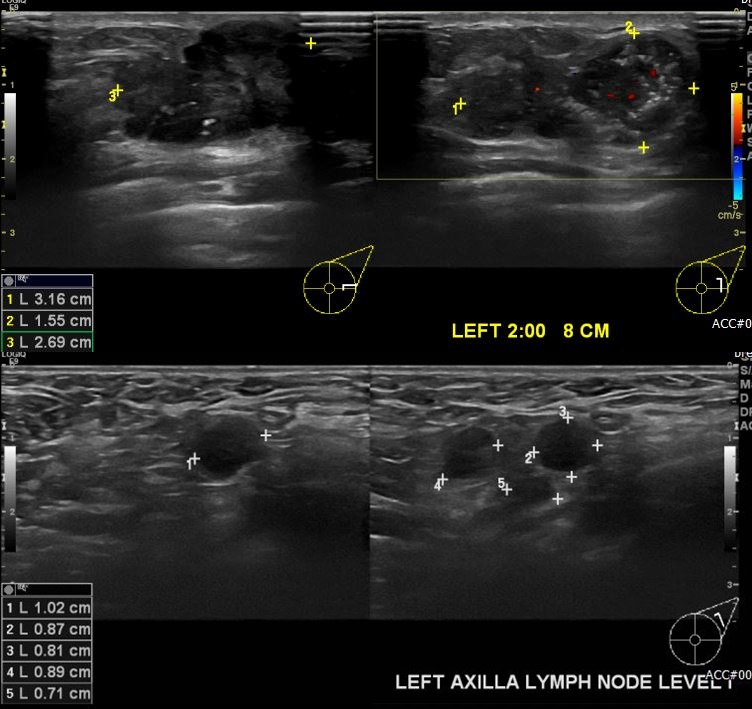

상기환자 몇개월전 만져지는 멍울로 내원하신 40대 여성분으로 좌측 2시방향 8cm

떨어진 거리의 만져지는 멍울 조직검사 시행하여 좌측 침윤성 유관암 진단 되었으며,

좌측 겨드랑이  림프절 비대  세침검사 시행하여 전이암 진단 되었습니다.